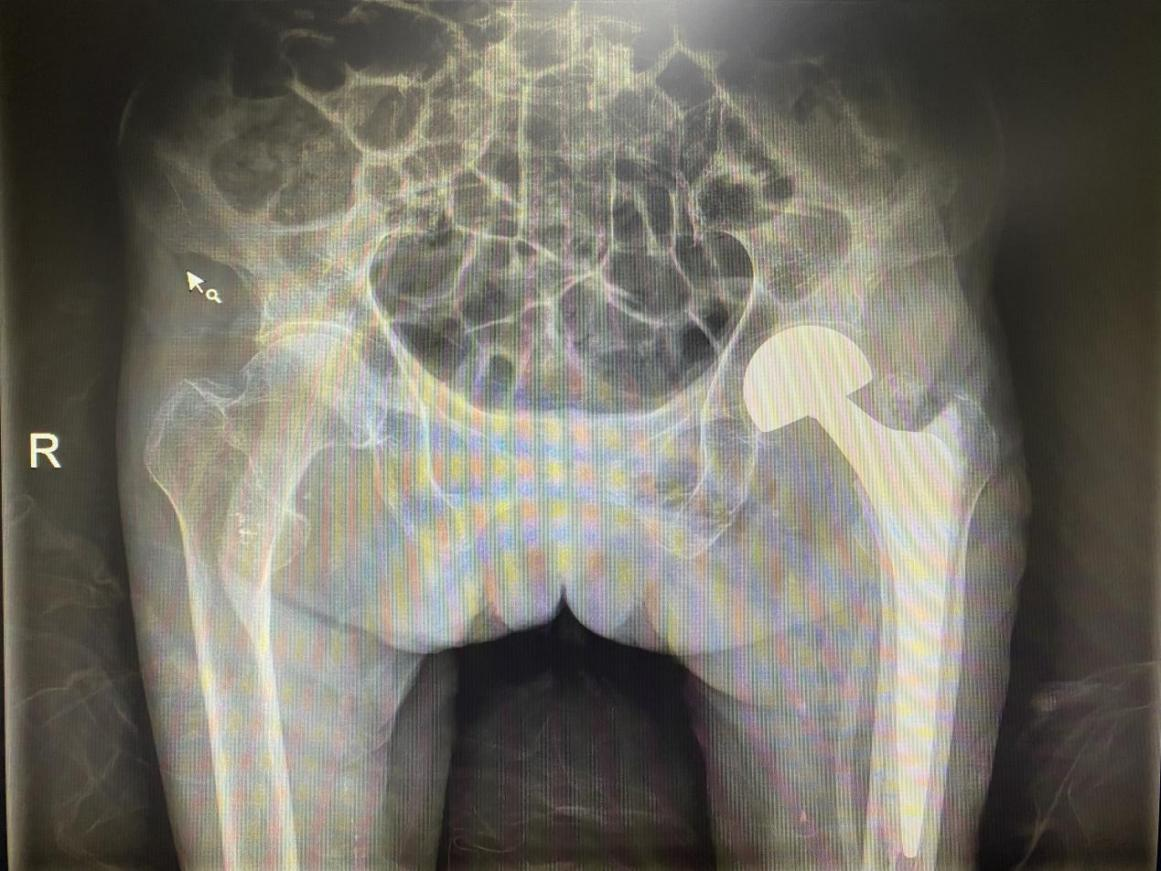

莫奶奶已经100岁高龄且有多种自身疾病,行手术风险极高;如果保守治疗,老人可能因为长期卧床发生肺部感染、压力性损伤、下肢深静脉血栓等严重并发症,不但严重影响生活质量,甚至会危及生命。为了莫奶奶能有一个安全有效的治疗,我院脊柱关节骨病外科联合麻醉科经过详细讨论,制定出个体化手术方案。经家属同意治疗后,于2021年03月05日为莫奶奶进行了左侧人工股骨头置换术,手术仅用一个多小时。术后在医护人员精心治疗和护理下,指导老人进行下肢功能锻炼,老人恢复良好,精神面貌焕然一新。术后第二天莫奶奶就能在康复师指导下使用助行器行走,术后一周康复出院。“极限”手术挑战成功,百岁老人重获“新生”。为了表达对科室医护人员的感激之情,莫奶奶家属为我院脊柱关节骨病外科及手麻科送来了锦旗与感谢信。

莫奶奶术后X线检查影像图片